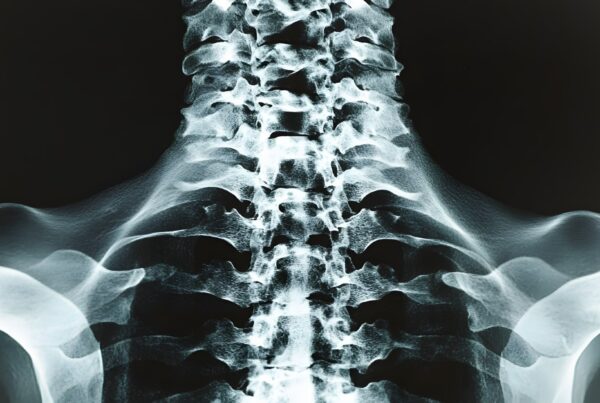

You feel fine, so why can’t you get back to all of your normal activities right away? It may seem like you’re having to be overly cautious when your herniated disc has initially healed, but there is still a great deal of repair going on at the surgical site. It doesn’t matter whether you’ve had a disc surgery performed in the cervical or lumbar region, or anywhere in between — any area along your spine is susceptible to reinjury if it is not properly cared for.